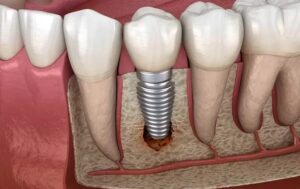

Профессиональная гигиена при имплантатах: как часто делать и почему это критически важно

Зубные имплантаты не боятся кариеса, но это не значит, что они не требуют ухода. Напротив, риск воспаления тканей вокруг имплантата выше, чем вокруг обычного зуба, а последствия могут быть гораздо серьезнее — вплоть до полной потери конструкции. В этой статье разбираем, как часто нужно посещать стоматолога для профессиональной гигиены, от чего зависит периодичность визитов и …

Имплантация зубов: путь к восстановлению улыбки и уверенности

Имплантация зубов – это современный и эффективный способ восстановления утраченных зубов. Этот метод позволяет не только вернуть эстетику улыбки, но и восстановить функциональность зубного ряда, улучшить качество жизни. Больше информации можно узнать на сайте https://factorsmile.ru/uslugi/implantatsiya/. Что такое имплантация зубов? Имплантация зубов – это хирургическая процедура, в ходе которой в костную ткань челюсти вживляется титановый имплантат, …

Имплантация зубов: современные методы восстановления улыбки

Имплантация зубов – это современный и эффективный способ восстановления зубного ряда, который позволяет вернуть не только эстетическую привлекательность улыбки, но и полноценную функциональность зубов. Как выбрать метод имплантации зубов, мы подробно рассмотрим в этой статье, чтобы вы могли сделать осознанный выбор в пользу здоровья и красоты вашей улыбки. Что такое имплантация зубов? Имплантация зубов – …